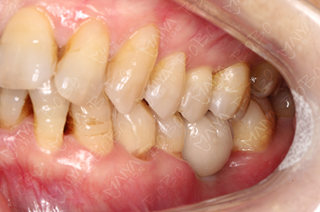

医生为赵阿姨检查牙齿情况

赵阿姨牙齿缺失情况